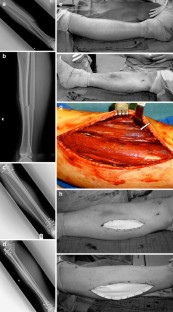

Fig. 1